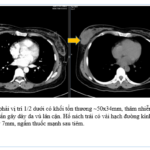

CASE LÂM SÀNG Điều trị bệnh nhân mắc đồng thời hai loại ung thư: Ung thư phổi và ung thư...

GS.TS Mai Trọng Khoa; BSNT Hoàng Mạnh Đức, Ths Bùi Quang Lộc , PGS.TS Phạm Cẩm Phương, Bsck II Hoàng Anh, Trung tâm y học hạt nhân và...